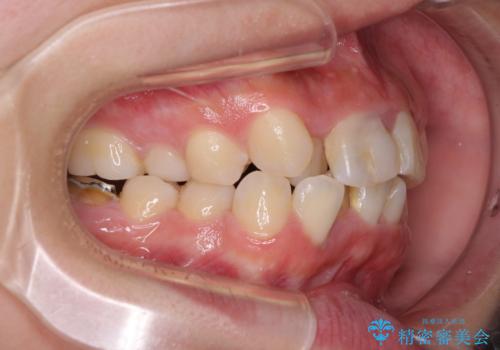

- 放置した虫歯や抜いたままの奥歯、前歯のデコボコを気にして来院された患者様です。

口元の突出感は少なく、下顎の叢生は軽微なものであったので、叢生の強い上顎左右の小臼歯を1本ずつ抜歯し、ワイヤー装置にて矯正治療を行うこととしました。